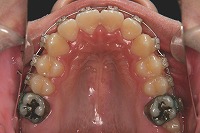

18歳7か月

上顎